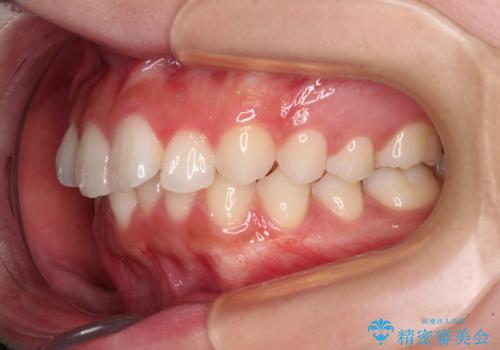

欠損した歯と前に飛び出した前歯 インプラント治療を併用したワイヤー矯正治療

- 上の前歯が下唇に当たる感覚と奥歯の欠損を気にして来院された患者様です。

上顎前歯の突出感は、上顎全体が前方に位置していることが原因であったため、補助装置により上顎全体を後方に移動させることとしました。

後方移動と同時上下歯列をワイヤー装置にて整え、奥歯の欠損部には矯正治療の途中でインプランを埋入していくこととしました。

上顎歯列全体を後方移動させたことで唇に当たる感覚は改善され、更には上下の正中位置も合わせることができました。